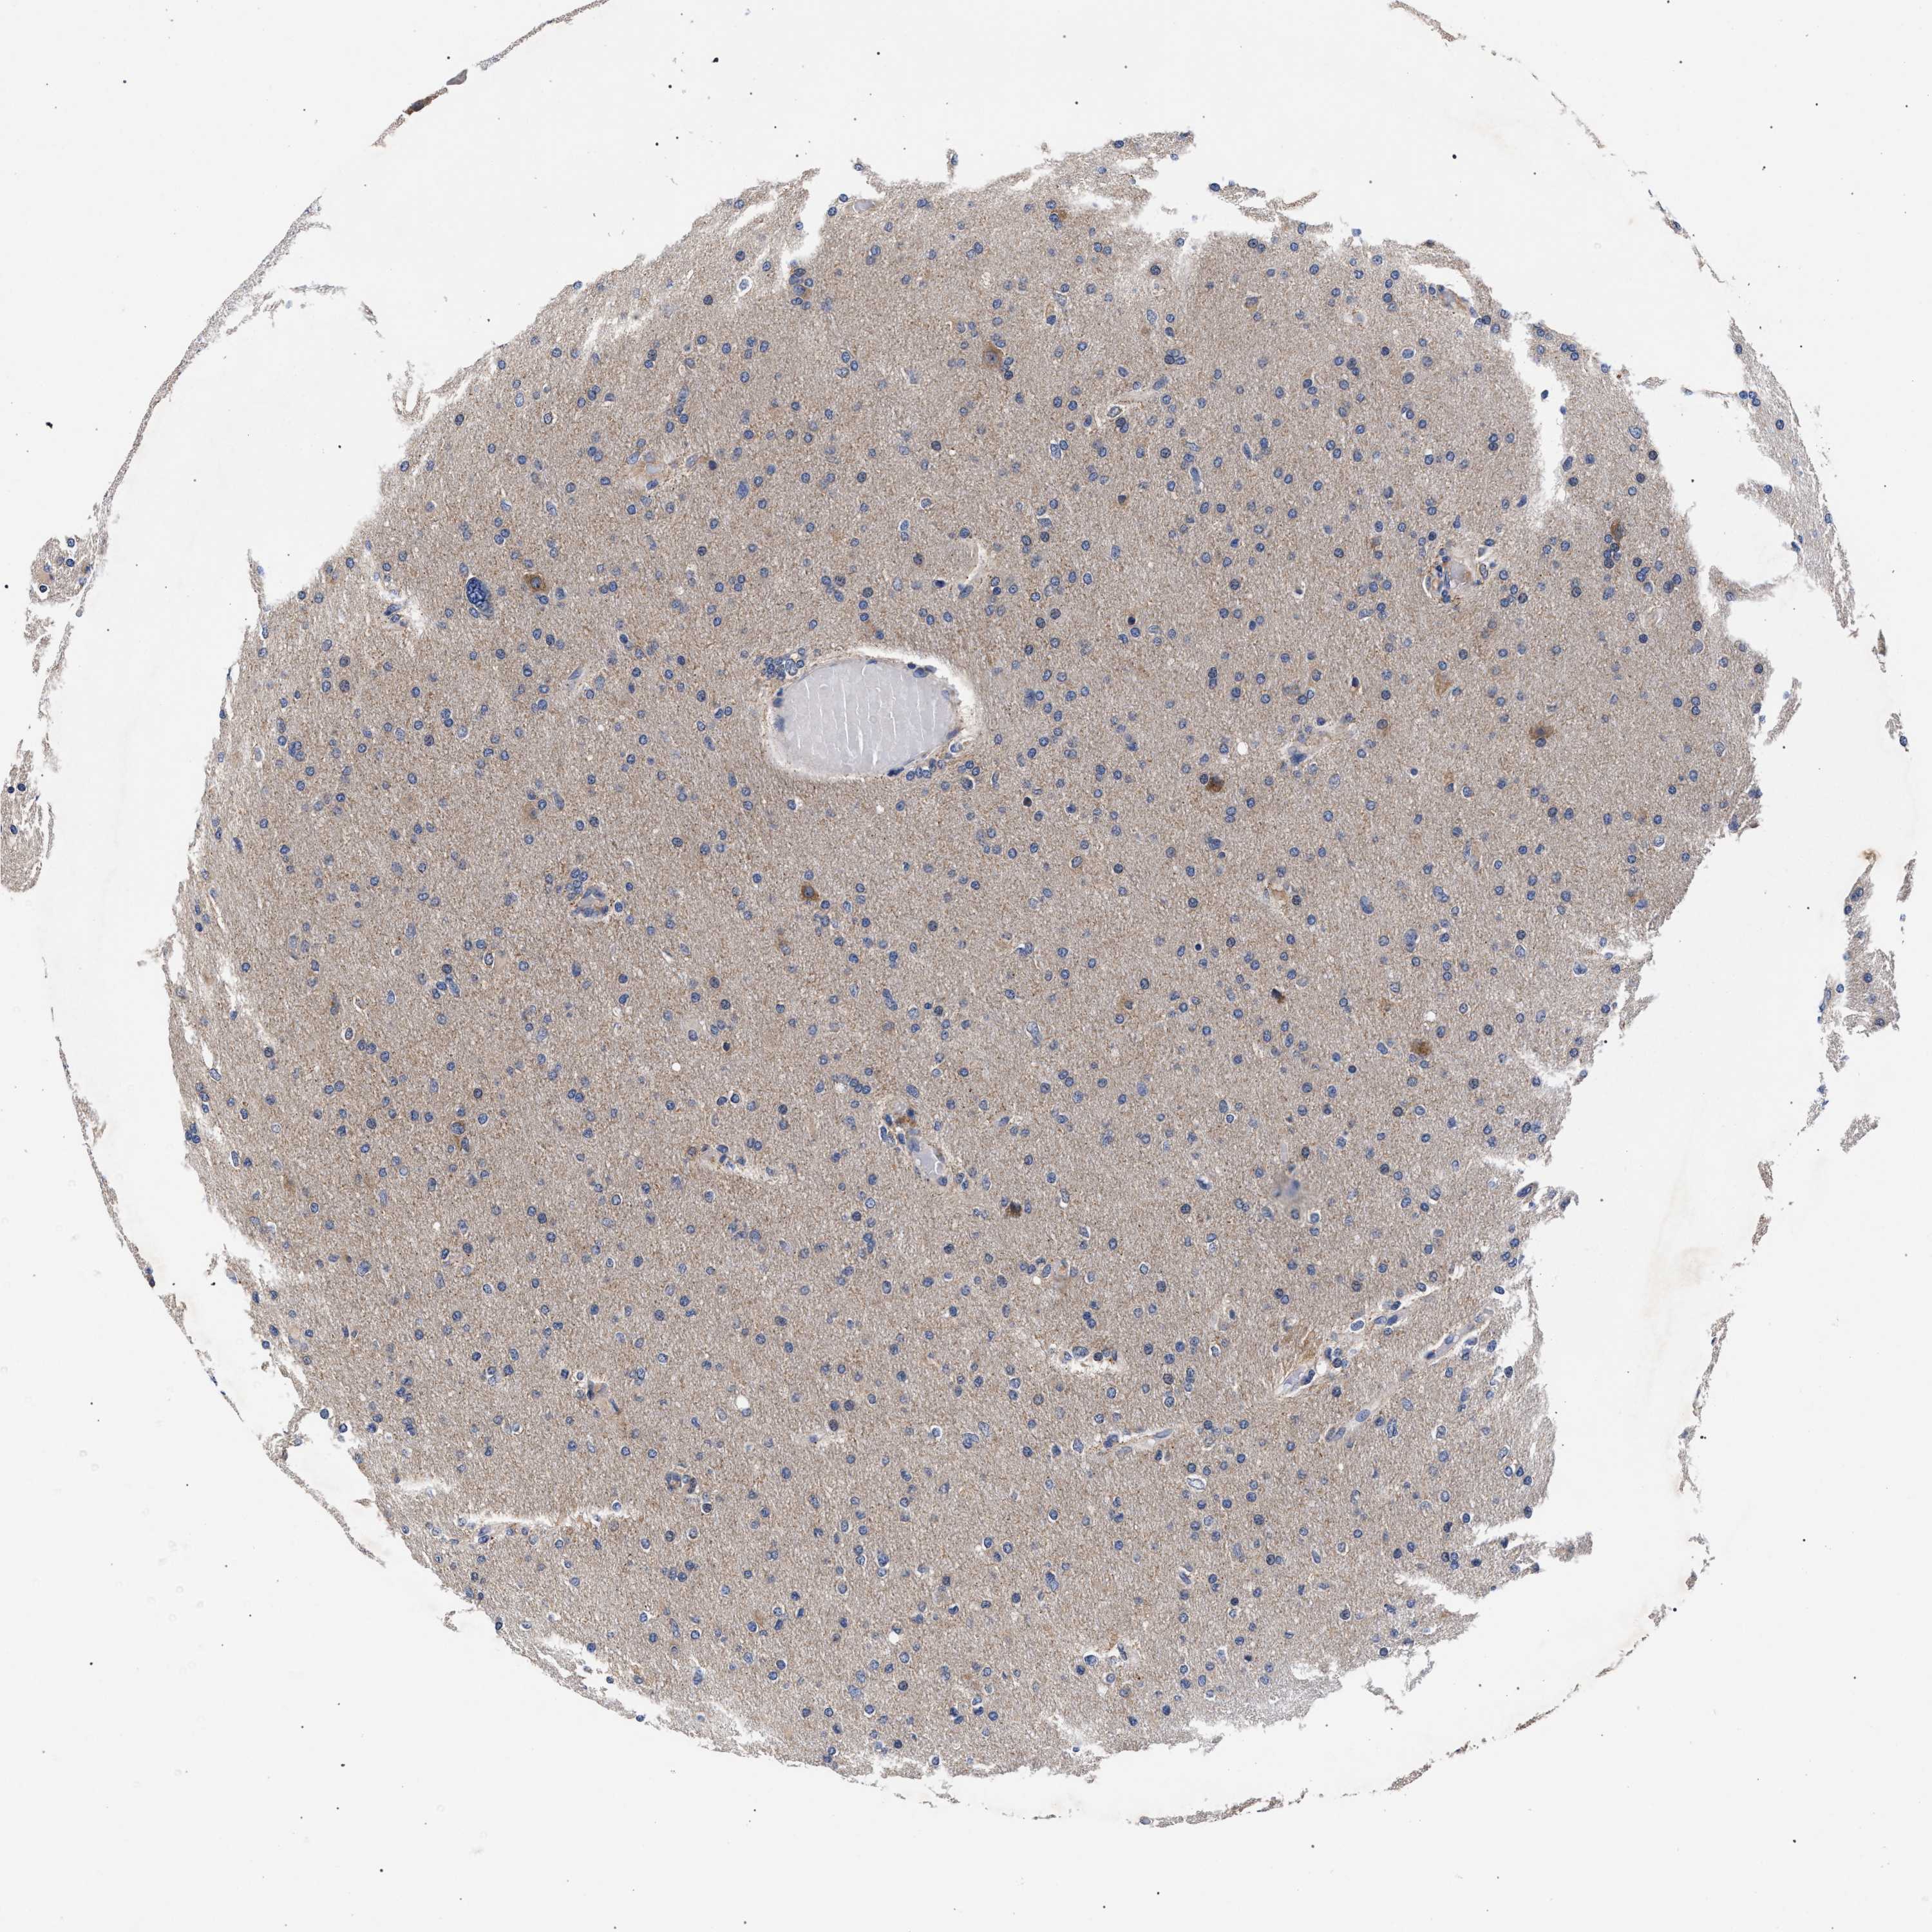

GLIOMA - Protein expressioni

A mouse-over function shows sample information and annotation data. Click on an image to view it in a full screen mode. Samples can be filtered based on level of antibody staining by selecting one or several of the following categories: high, medium, low and not detected. The assay and annotation is described here.

Note that samples used for immunohistochemistry by the Human Protein Atlas do not correspond to samples in the TCGA dataset.

Antibody stainingi

Antibody staining in the annotated cell types in the current human tissue is reported as not detected, low, medium, or high, based on conventional immunohistochemistry profiling in selected tissues. This score is based on the combination of the staining intensity and fraction of stained cells.

Each image is clickable and will lead to virtual microscopy that enables deeper exploration of all samples and also displays staining intensity scores, fraction scores and subcellular localization as well as patient and tissue information for each sample.

Antibody HPA021261

Antibody HPA021325

Staining

High

Medium

Low

Not detected

Intensity

Strong

Moderate

Weak

Negative

Quantity

>75%

75%-25%

<25%

None

Location

Nuclear

Cytoplasmic/membranous

Cytoplasmic/membranous,nuclear

Glioma, malignant, High grade

Glioma, malignant, Low grade